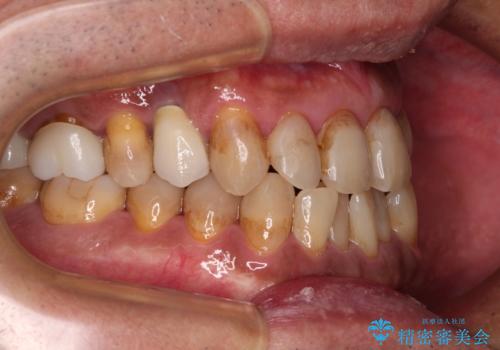

今からでも綺麗な歯並びを手に入れたい 40代男性のワイヤー矯正

- 前歯のクロスバイトを気にして来院された患者様です。

40代男性で、インプラント補綴治療も経験されている方で、矯正治療をしても良いのかと悩んでいらっしゃいました。

下顎骨の左右のずれがあり、下顎全体が前方に出ている状態であったので、無理をせずにワイヤー装置にて矯正治療を行うこととしました。

クロスバイト改善には難儀しましたが、咬みやすく、笑ったときに清潔感ある口元に仕上げることができました。